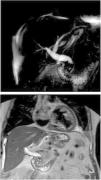

The second patient presented a slight alteration of the hepatobiliary-pancreatic profile. CT scan showed multiple hepatolithiases and stenosis of the hepatojejunal anastomosis, confirmed by MRCP (Image 5). A solely transparietal approach was performed, which confirmed abundant hepatolithiases, most of which could not be mobilized, so only the stenosis was treated by dilation with angioplasty balloons measuring 8 and 10 mm in diameter (Image 6). In a second stage, after multidisciplinary assessment (radiology and surgery), a transparietal approach combined with cholangioscopy was performed. In the cholangiography, some stones had been eliminated spontaneously, but a repletion defect persisted; during cholangioscopy, we confirmed that this defect corresponded with a clot. The rest of the biliary tree was explored until the anastomosis was passed, finding no residual hepatolithiasis. The patient progressed well, with no complications or recurrence after 6 months.